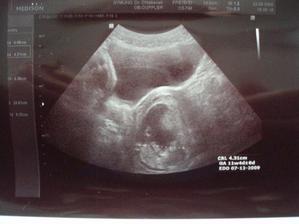

22.5. preventivni prohlidka u meho gynekologa. Vse OK. Mrnous ma od hlavicky k prdelce 4,3 cm, srdicko tluce 146 tepu za minutu. A je to stydlin, se k nam otocil prdelkou 😉